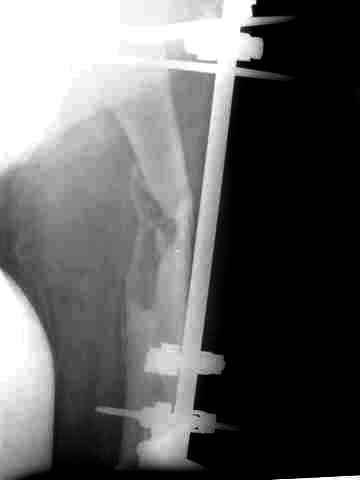

После нескольких некрэктомий, проведения аутодермопластики и заживдения ожоговой раны через 2 месяца после травмы произведен открытый остеосинтез левой бедренной кости штифтом и пластиной (деротационной) [image 01, 02]. Через 1 год и 7 месяцев после травмы у больного диагностированы ложный сустав и хронический остеомиелит левой бедренной кости. Произведено удаление металлических фиксаторов, секвестрэктомия и остеосинтез бедренной костивнешним двухплоскостным стержневым аппаратом [image 03, 04] .

Через 3 года после травмы констатировало отсутствие консолидации бедренной кости, сохранение признаков хронического остеомиелита (свищ в нижней трети левого бедра). Произведен демонтаж аппарата, реостеосинтез бедренной кости спице-стержневым аппаратом, некрсеквестрэктомия. В аппарате удалось лишь частично произвестиустранение углообразной деформации бедренной кости [image 05] .

Через 4,5 лет после травмы выявлены рентгенологические признаки консолидации перелома, признаки хронического остеомиелита купировались. Аппарат был демонтирован. Пациент продолжил ходьбу с дозированной нагрузкой на конечность при помощи костылей. Через 2 месяца начал ходить при помощи трости. Однако, еще через 2 месяца отметил появление свищей на бедре с гнойным отделяемым и укорочение длины конечности. При осмотре в январе 2007 г.: пациент ходит при помощи костылей без опоры на левую нижнюю конечность, на бедре имеются множественные рубцы, на наружной поверхности сегмента в верхней и нижней третях имеются два свищевых хода со скудным серозно-гнойным отделяемым; отечности тканей конечности нет, пальпация безболезненная, отмечается укорочение длины конечности на 5 см, патологическая подвижность не определяется, имеется стойкая разгибательная контрактура коленного сустава (разгибание - 180 гр, сгибание - 170 гр), признаков нарушения кровоснабжения и иннервации тканей конечности нет. Температура тела нормальная. В общих анализах крови и мочи отклонений от нормы нет. [image 06,07, 08 (стрелками отмечены свищевые раны, 09, 10]Дорогие коллеги, я уверен, что у многих из вас после знакомства с данным клиническим наблюдением появится множество вопросов, касающихся уже проведенного лечения (особенно, сроков и способов). Сразу оговорюсь - я не смогу правильно ответить на многие вопросы (особенно касающиеся предшествующего периода лечения). Прошу вас, конечно по возможности, сосредоточить внимание не на разборе допущенных ошибок (проведенного лечения), а помочь добрым советом относительно тактики наших дальнейших действий. Наверное, кто-то располагает бесценным опытом лечения подобной патологии.